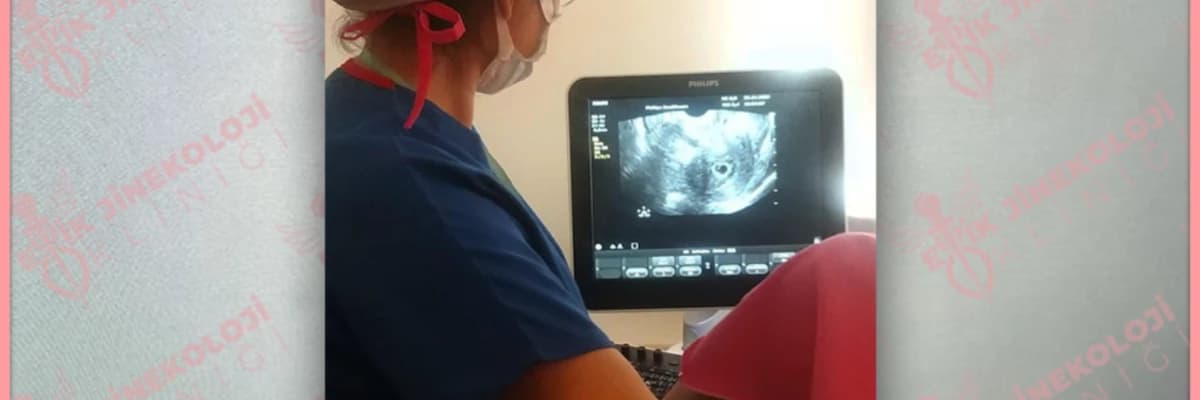

Temel vajinal ultrasonografi yanında bazan rahim boşluğuna sıvı vererek çekilen sonohisterogram da yapılabilir. Ultrason görüntüsü karar vermeye yetmezse bazan MR gerekebilir.